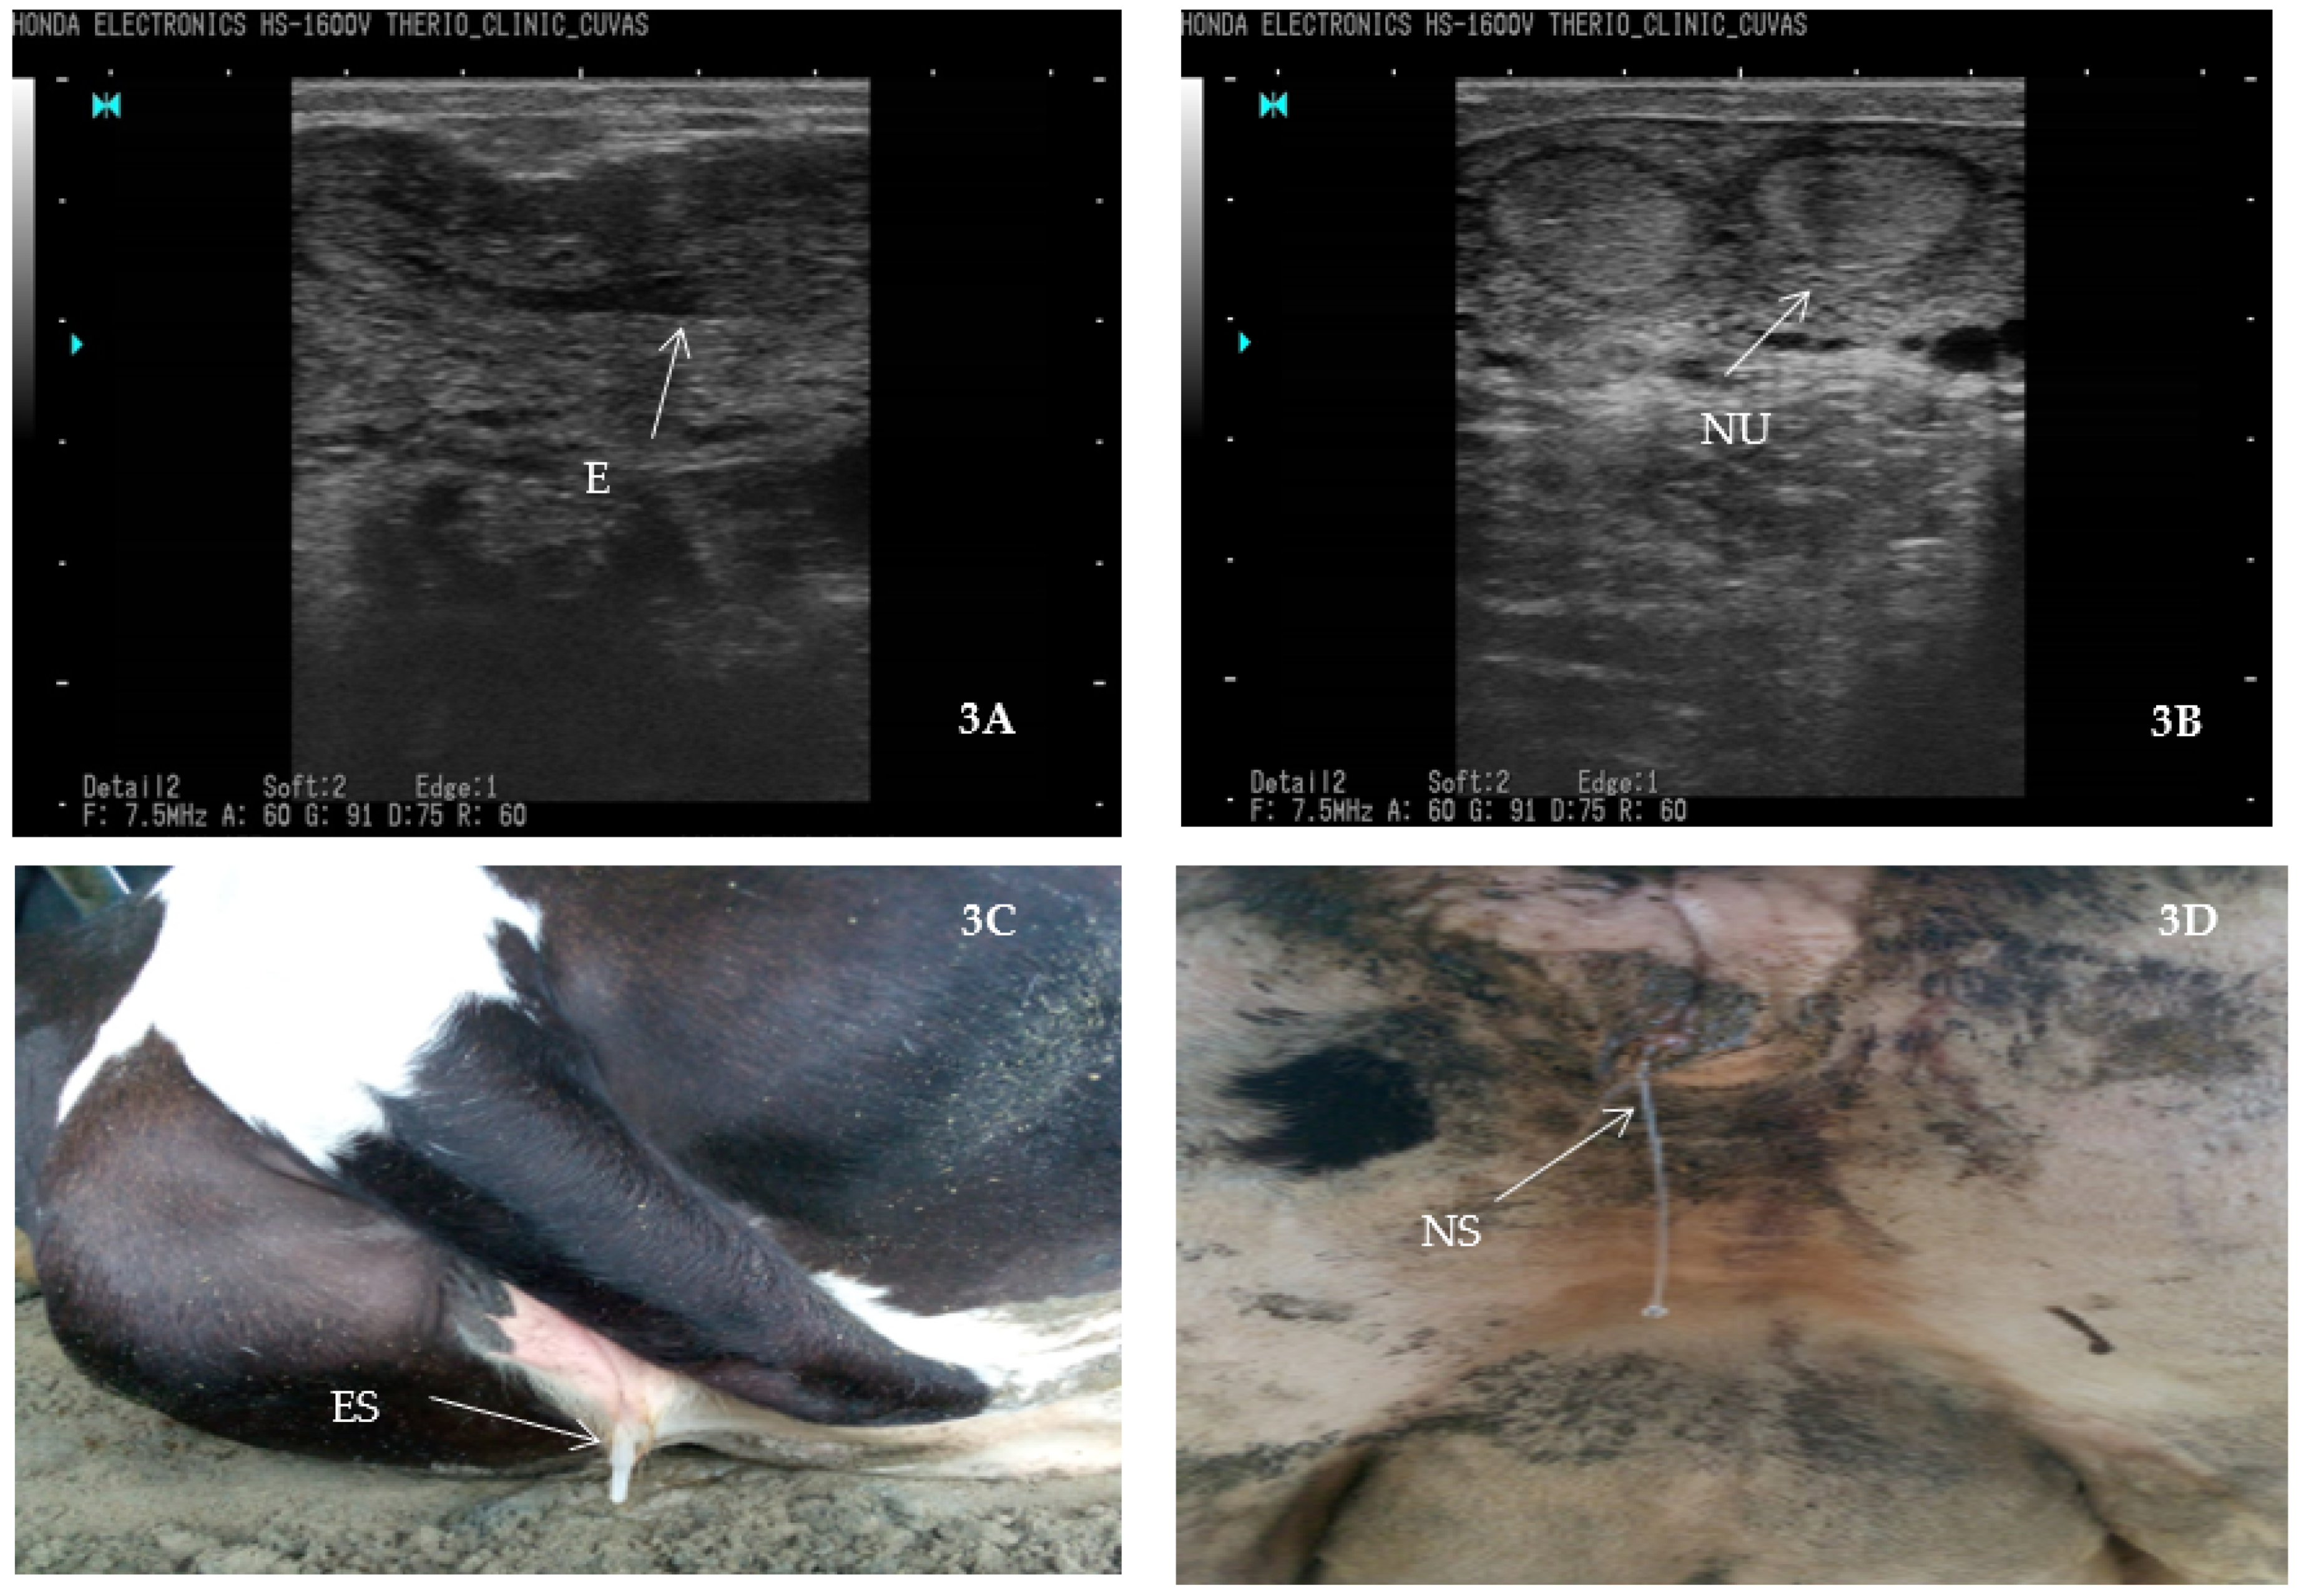

4.6.1. Tracking Bovine Endometritis

- Fissore, R.A.; Edmondson, A.J.; Pashen, R.L.; Bondurant, R.H. The use of ultrasonography for the study of the bovine reproductive tract. II. Non-pregnant, pregnant and pathological conditions of the uterus. Anim. Reprod. Sci. 1986, 12, 167–177. [Google Scholar] [CrossRef]

- Ihnatsenka, B.; Boezaart, A.P. Ultrasound: Basic understanding and learning the language. Int. J. Shoulder Surg. 2010, 4, 55. [Google Scholar]